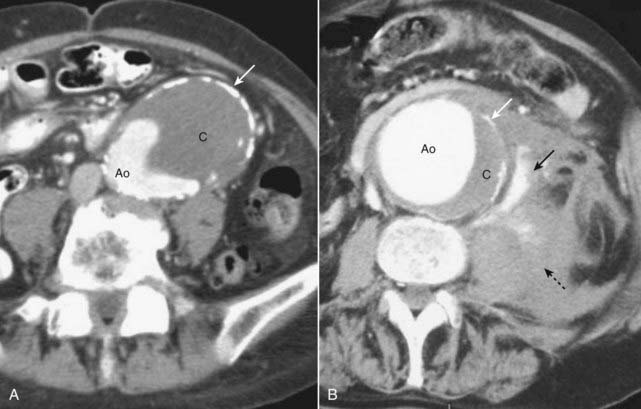

Figure 19-13 Abdominal aortic aneurysms on CT: mural thrombus and rupture.

A, The aorta is enlarged. Contrast is present in the lumen (Ao) along with a large clot (C). Calcification is seen in the wall of the aorta (solid white arrow). The aneurysm is almost in contact with the anterior abdominal wall. B, This aneurysm, in another patient, has ruptured. Contrast is seen in the lumen (Ao) along with a crescentic clot (C), and there is calcification present in the wall (solid white arrow), just as in the previous case. The major finding here is active extravasation of contrast-containing blood outside of the aorta (solid black arrow) producing a large retroperitoneal hematoma (dotted black arrow).